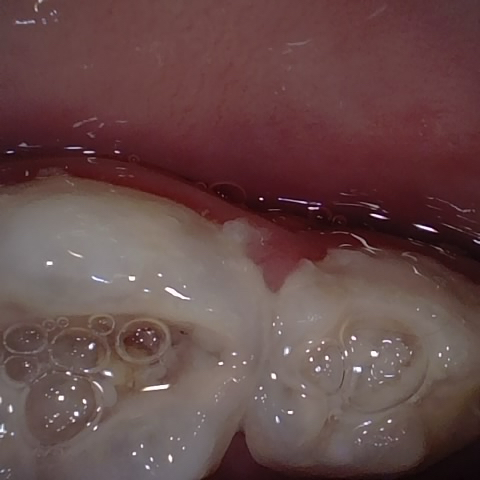

NHD25463

Annotated as "Bad"